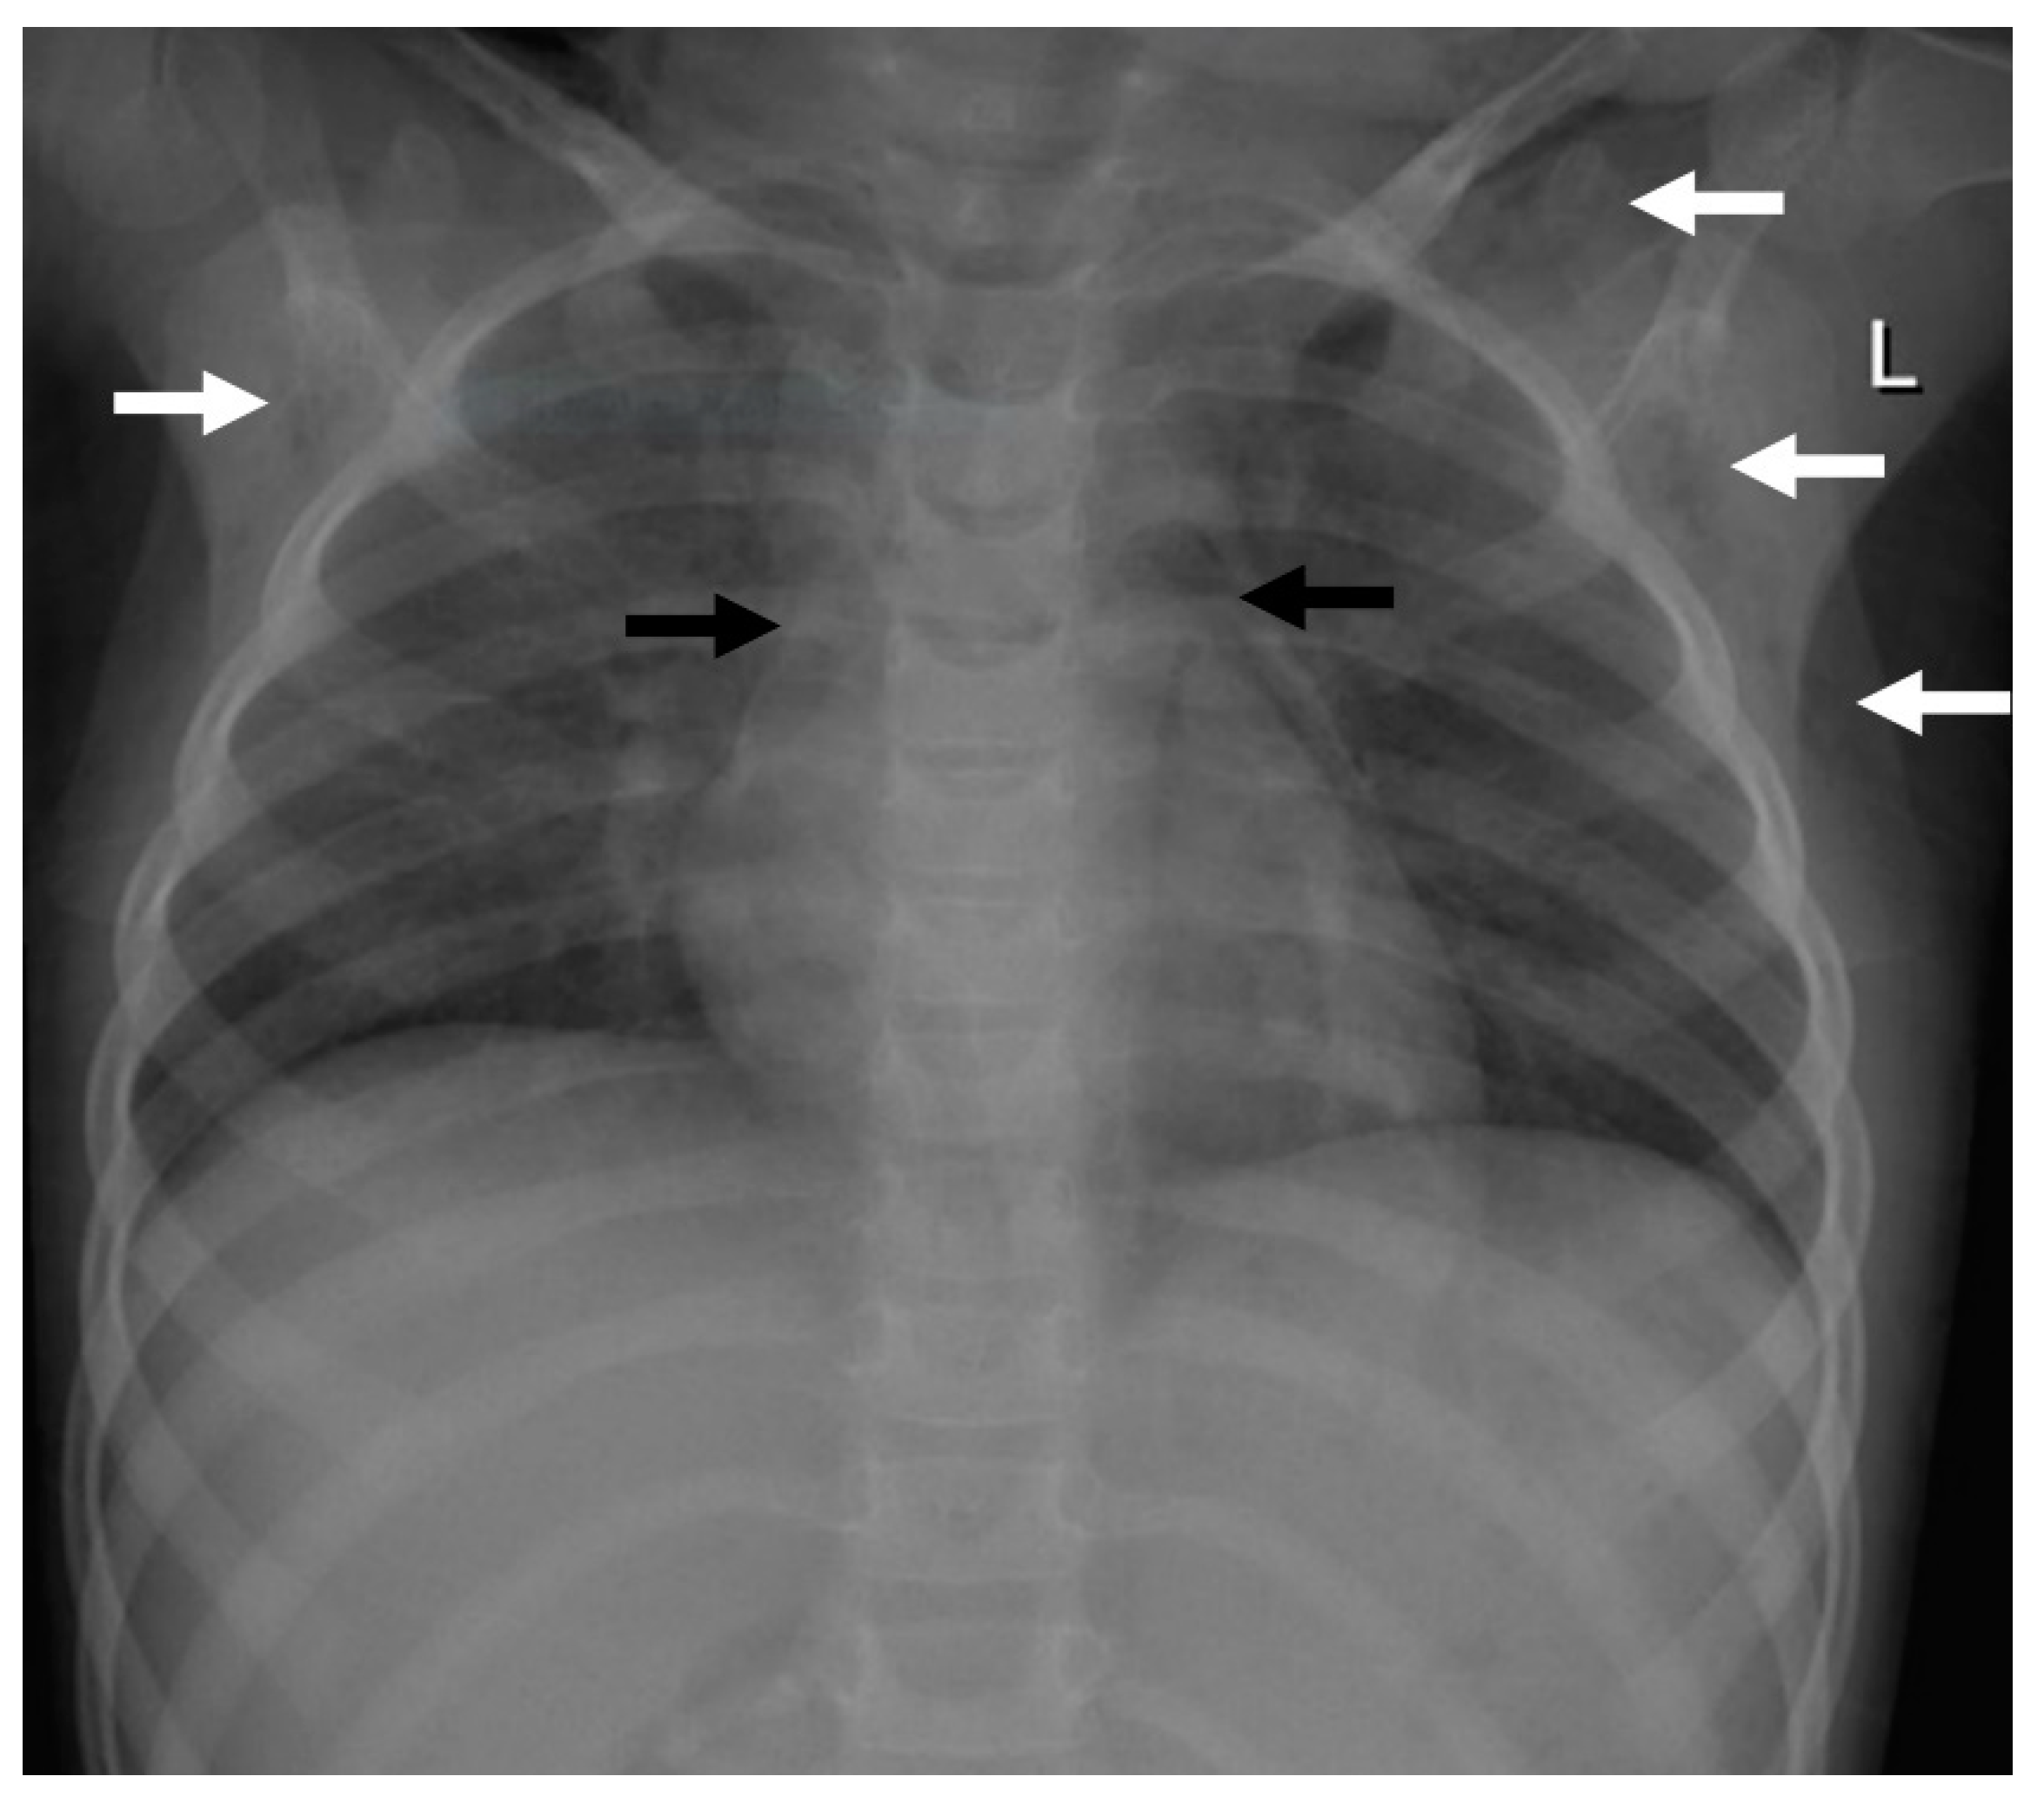

Figure 1.

Imaging findings in patient 1. Chest X-ray showing a pneumomediastinum (black arrows) and a subcutaneous emphysema, more pronounced on the left site (white arrows).